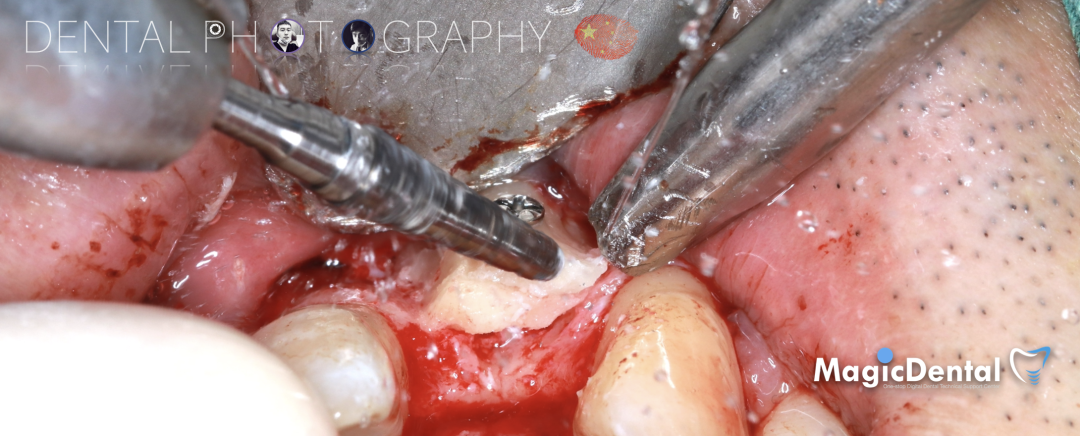

切开翻瓣,彻底暴露术区,试戴骨块。

调整骨块外形,适配受植区域,打开骨髓腔。

预备固位钉洞,固定骨块

骨膜减张,放置骨粉,放置骨块,钛钉固定骨块。

固定骨片,修整骨块边缘,继续放置骨粉覆盖骨块及受植区,放置骨膜,严密缝合创口。

制作种植导板,局麻下切开,翻瓣彻底暴露术区,取出骨钉。

导板就位,种植窝洞预备,植入Nobel Active 3.5*15mm种植体一枚,植入扭矩35N,安装临时基台。